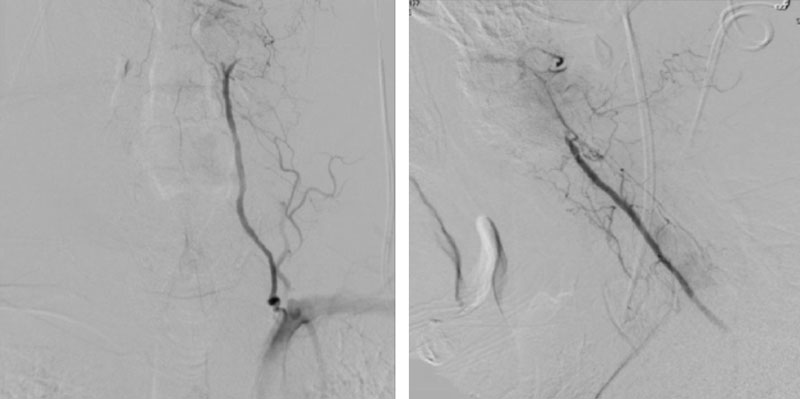

We performed conventional catheter angiography with provocative testing to reproduce his symptoms. The right Vertebral Artery is the codominant primary supply to the basilar circulation with reflux into the distal left Vertebral Artery that is occluded (Figure 3).

During neutral positioning, the vertebrobasilar circulation fills briskly from the Right Vertebral Artery. (Figure 4)

On rotation to the left, the patient experienced mild symptoms, however no significant Vertebral Artery or basilar reduction in flow was observed. On rotation to the right, the patient experiences slightly more moderate symptoms, however no significant Vertebral Artery or vascular reduction flow was observed. On hyper extension of approximately 10-15 degrees, passively performed by the patient until symptoms are reproduced, angiogram demonstrates complete occlusion of the right Vertebral Artery at approximately the C2-C1 level. (Figure 5)